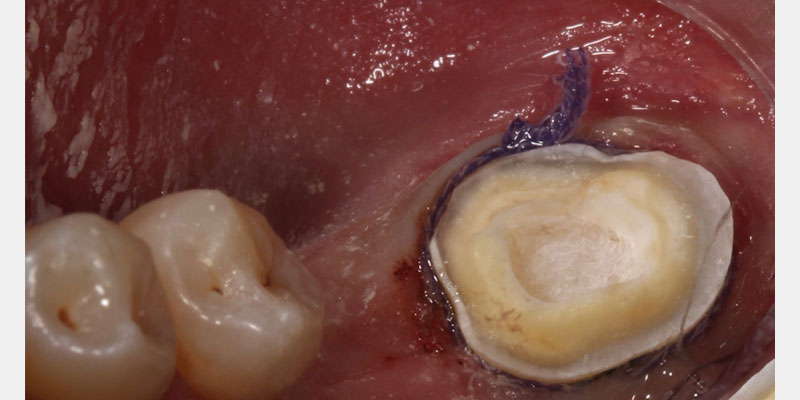

Since the early work on endocrowns was published by Bindl and Mormonn, a host of other studies have looked at preparation design for endocrown restorations. When preparing a tooth for an endocrown, a 2.0 mm occlusal reduction with extension into the pulp chamber is required.

The literature suggests a shoulder and a chamber finish line2, 3, 4 with the extension into the pulp chamber protruding approximately 2.0 mm into the chamber.5 Minimal retention is present, and thus, these restorations must be bonded in place with resin cement.

Endocrown restorations can be designed and fabricated using CAD/CAM technology and delivered in a single-visit appointment. Fabricating a provisional can be challenging due to the lack of traditional retentive features in an endocrown preparation. Studies performed that have involved fabricating a provisional for an endocrown preparation have utilized various materials, including Cavit-1 and acrylic-based provisional materials.6